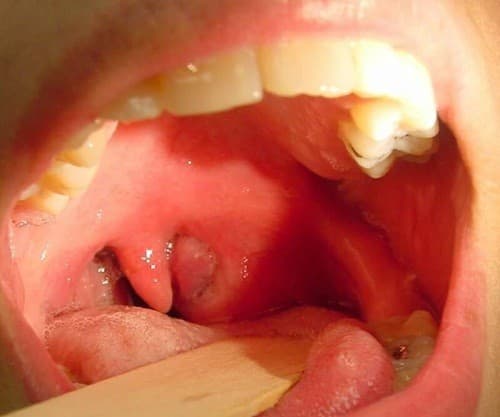

Viêm amidan là nhóm bệnh hay gặp, đứng hàng đầu trong những bệnh lý về họng. Bệnh có thể tiến triển cấp tính hay mạn tính. Viêm amidan cấp là bệnh thường gặp trong tình trạng nhiễm trùng còn phổ biến ở nước ta.

Viêm amidan là nhóm bệnh hay gặp, đứng hàng đầu trong những bệnh lý về họng. Bệnh có thể tiến triển cấp tính hay mạn tính.

Tỷ lệ bị bệnh khoảng 10% dân số. Viêm amidan rất hay tái phát và có thể gây các biến chứng nguy hiểm cho người bệnh, đặc biệt đối với trẻ em.

Đây là phương pháp được áp dụng trong trường hợp viêm amidan mạn tính. Phẫu thuật cắt amidan được chỉ định trong trường hợp viêm amidan quá phát nhiều lần trong năm, viêm amidan đã có biến chứng hoặc gây tắc nghẽn đường thở, ảnh hưởng tới sức khỏe người bệnh.